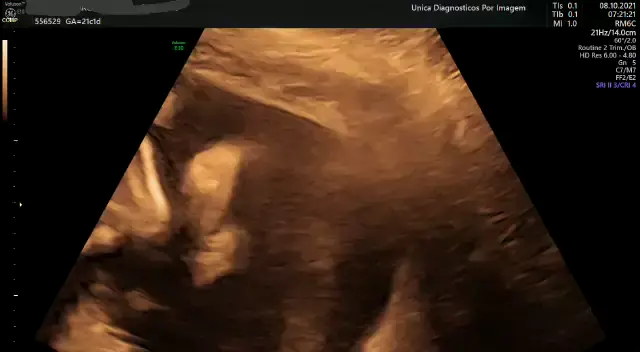

Unica diagnóstico por imagem

ultrassom obstetrico